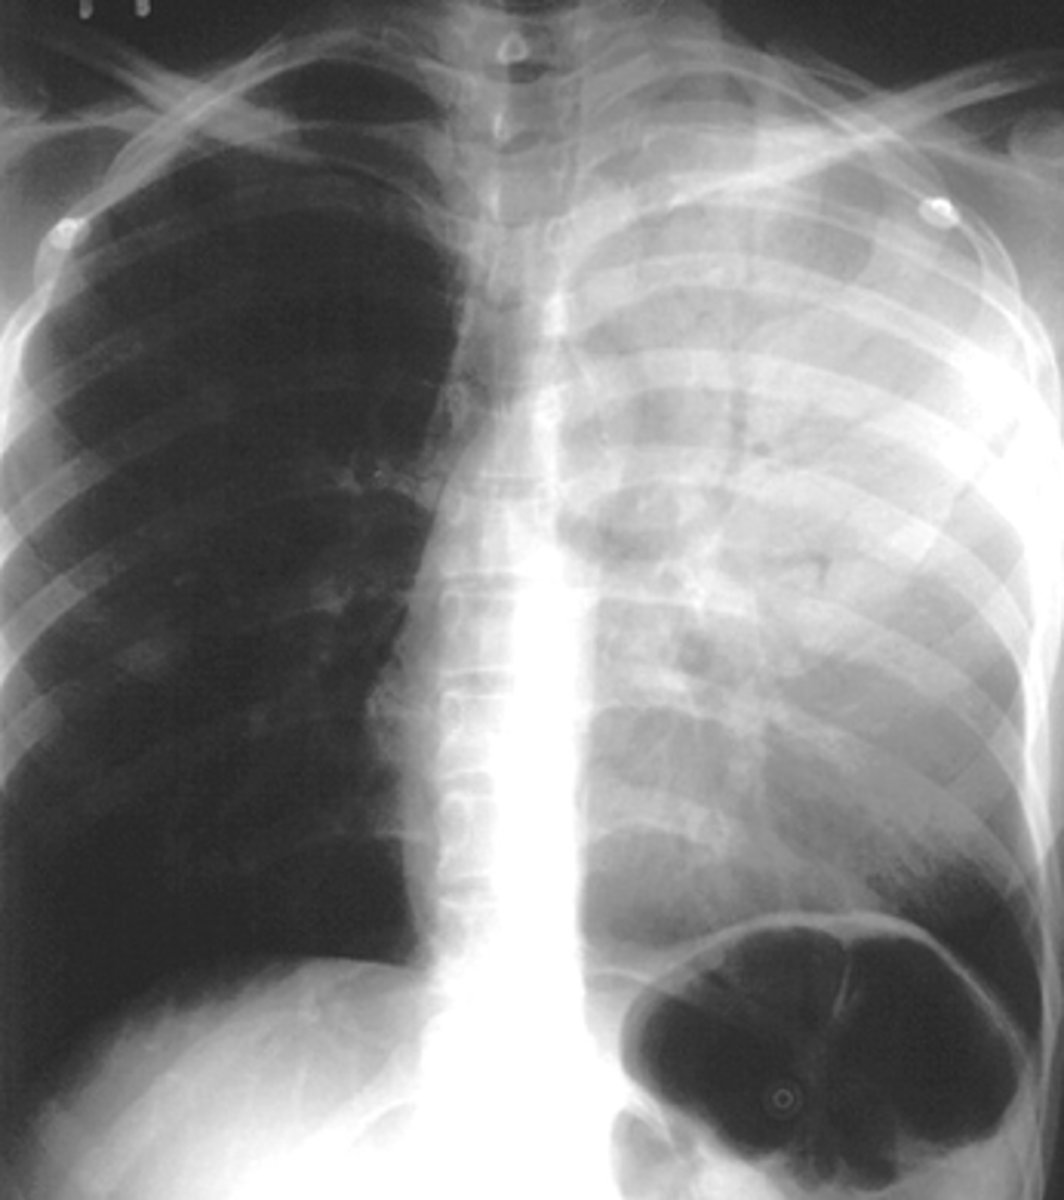

Silhouette sign right cardiac border- RML infiltrate

Silhouette sign right cardiac border, RML